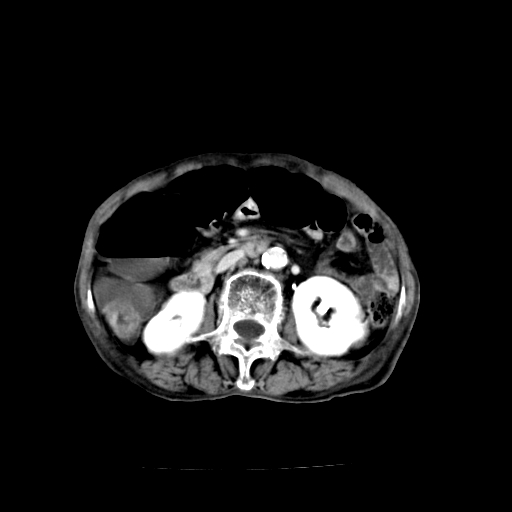

标题: CT19149:女,68岁,腹胀、恶心两周。 [打印本页]

标题: CT19149:女,68岁,腹胀、恶心两周。

女,68岁,腹胀、恶心两周,先做ct平扫,当时家属不同意强化,6天后家属要求增强扫描。

1)不排除胃窦癌;建议行胃镜检查。 2)局灶性脂肪肝。腹水。

考虑:胃窦ca,腹水,脂肪肝

支持考虑1、胃窦癌?建议行胃镜!; 2、局灶性脂肪肝。  3、双侧胸腔积液,胸膜增厚